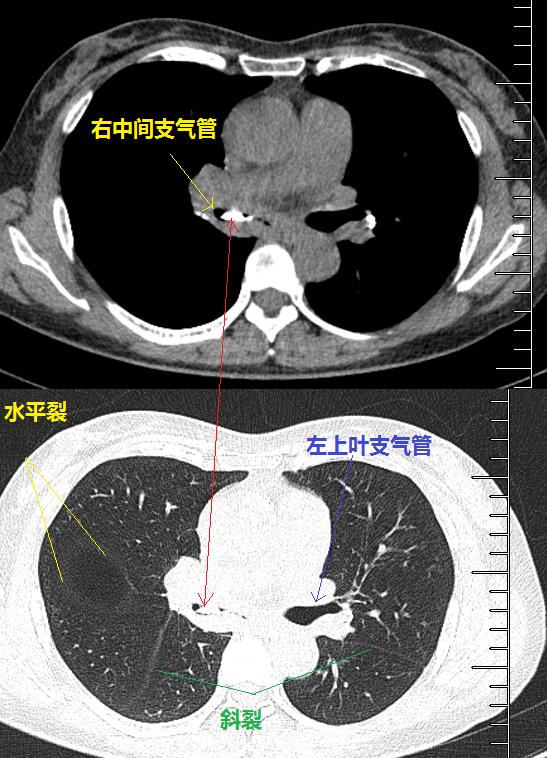

图10~图15 胸部CT示双肺多发钙化灶

问题出在哪儿?

右中间支气管的钙化病灶向外移动,钙化病灶的尖端刺激到支气管粘膜了(图16)。

图16 胸部CT

另外,这个患者的钙化灶非常危险,因为钙化灶的一端距离肺动脉才2毫米左右(图17),支气管镜下强行牵拉钙化病灶很可能会大出血危及生命。

图17 胸部CT